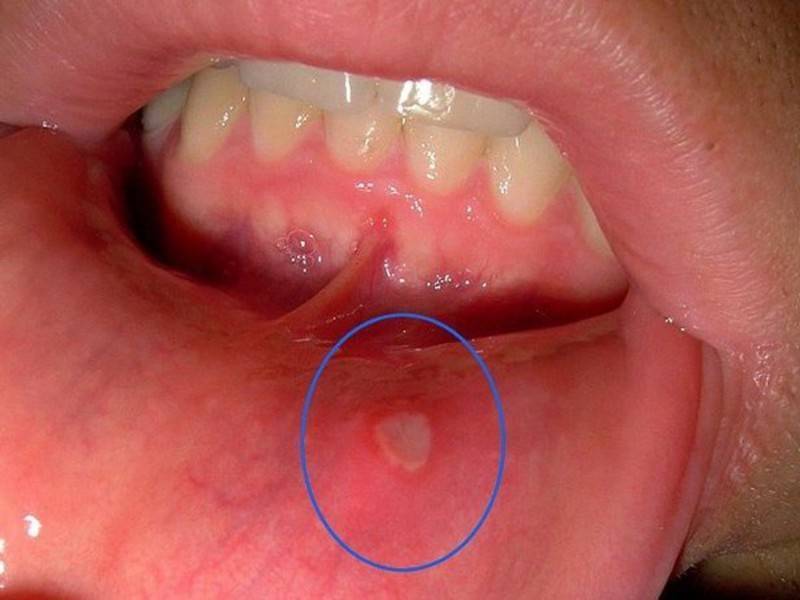

- Афтозного стоматита (кандидоза слизистой оболочки рта)

- афтозный стоматит

Причина жжения во рту: кандидоз.

- Жжения во рту особенно ощутимо при употреблении острой и кислотосодержащей пищи. Стоматолог определит афтозный стоматит и по наличию неприятных ощущений и по творожистым образованиям в полости рта пациента. Как правило, противогрибковая терапия приводит к исчезновению симптома жжения во рту

Причина жжения во рту: афтозный стоматит.